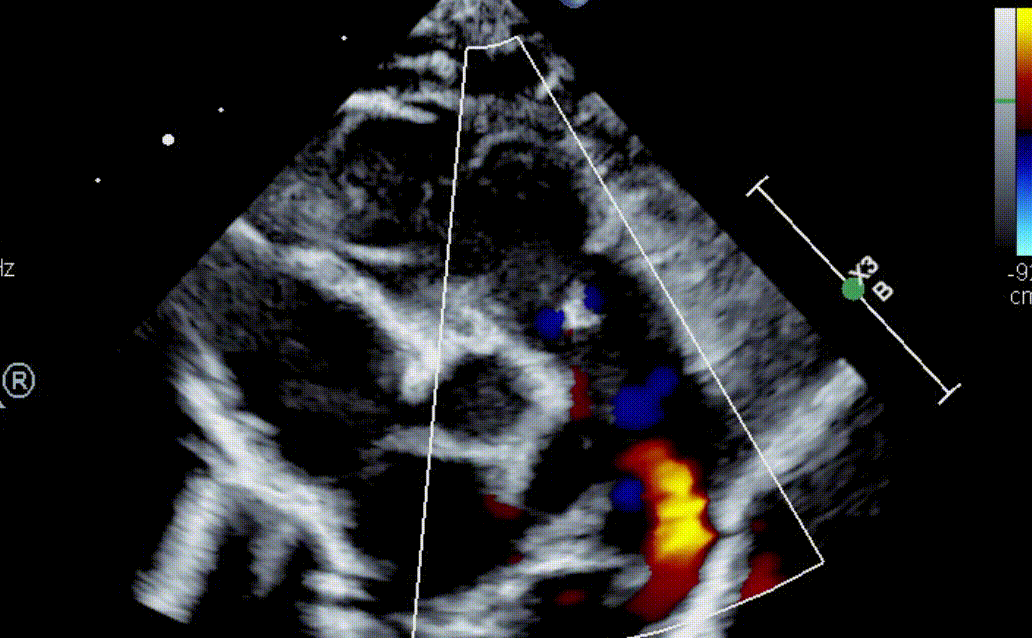

What congenital defect is shown here?

What is Absent Pulmonary Valve